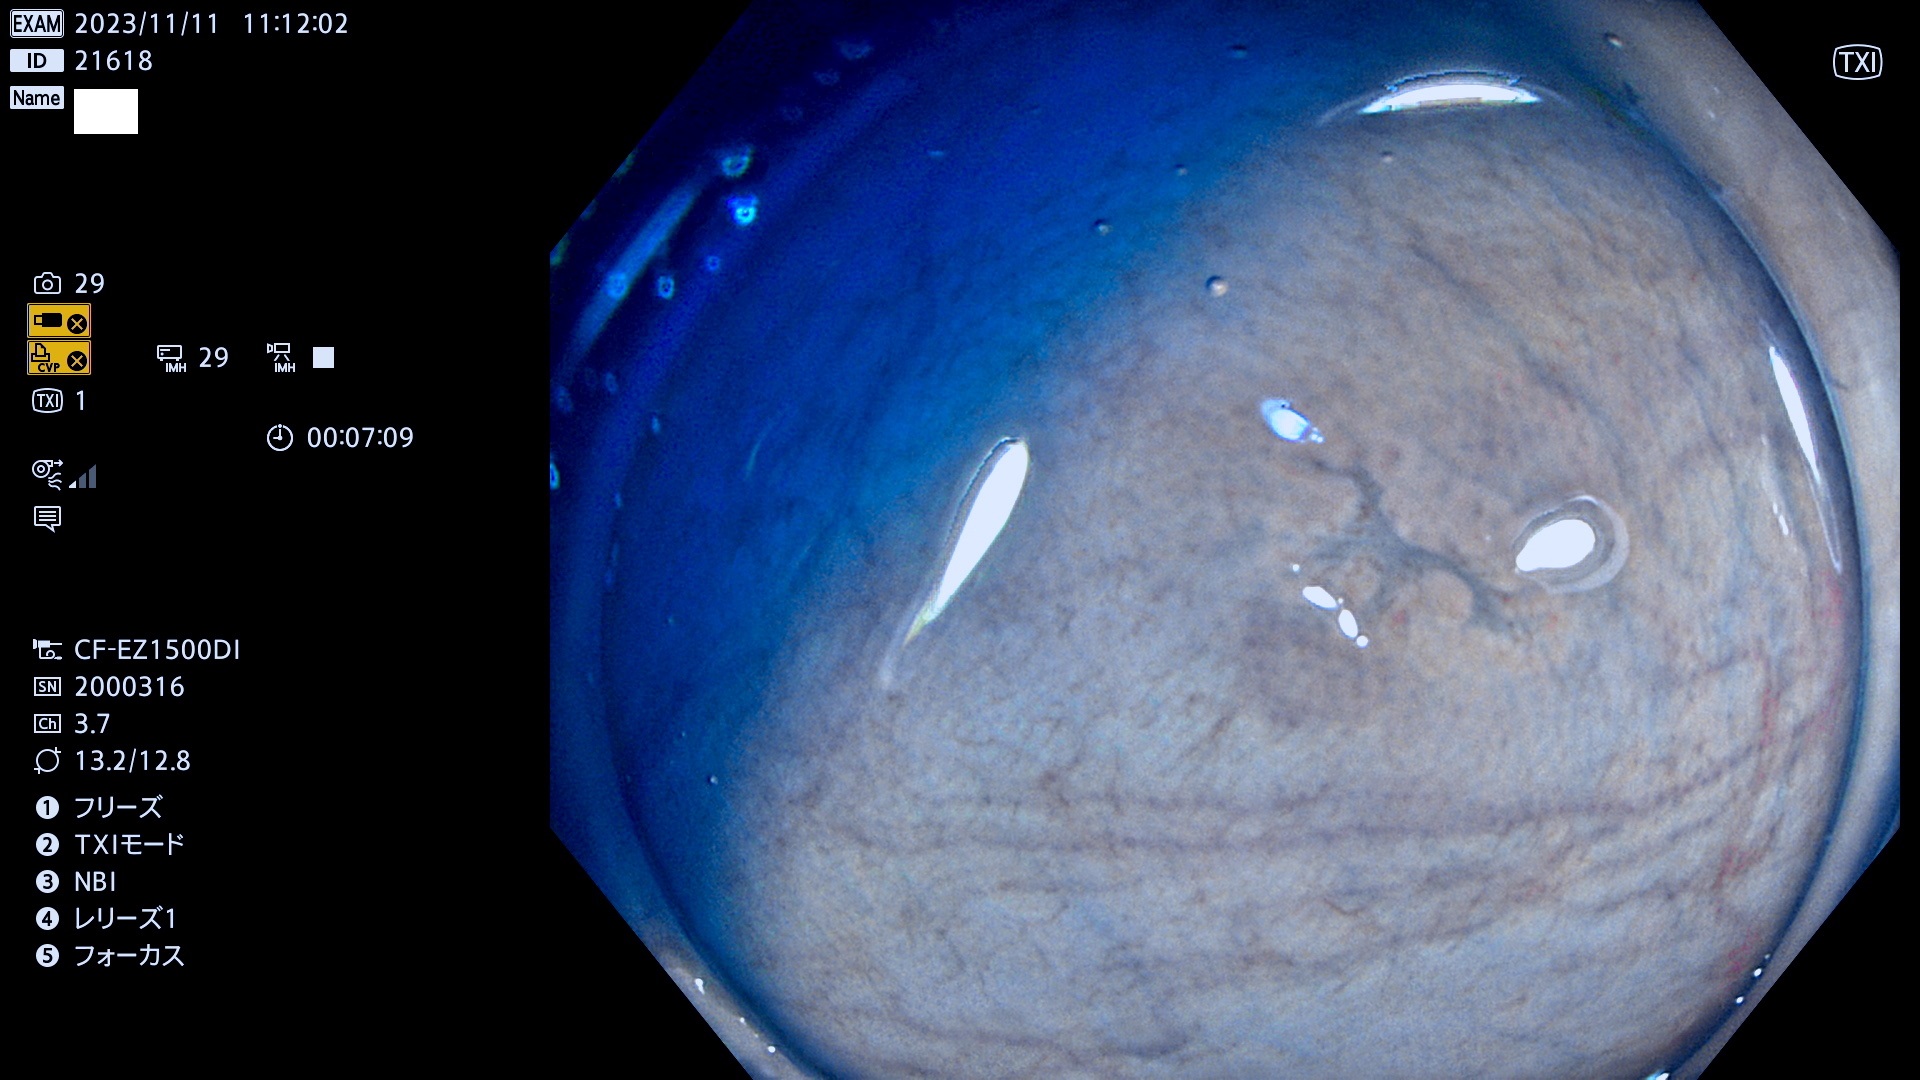

表面型腺腫(Flat Adenoma)の中で、完全に平坦な物をUb、陥凹している物をUcと呼びます。平坦隆起型(Ua)よりも、発見が難しく危険な病変です。このタイプは「内視鏡後・大腸癌の重要犯人」であり、この発見率は「腺腫発見率」よりも、重要な意味があります。

毎週の検査(木・金・土・日)に発見されたUb、Uc型・腺腫を、その週の日曜の夜にUPし1週間、提示します。

抽出の対象期間 2023年11月9日(木)〜11月12(日)の4日間(48件の検査)5件